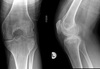

45

Name 4 major radiographic features on this radiograph.

- generalized osteopenia - widening of intercondylar notch - uniform jt space loss - ballooning of epiphysis

46

Give 2 differentials in order of likelihood. What 2 features support your diagnosis?

1. Hemophilia 2. JIA - ballooning of epiphysis - squaring of patella